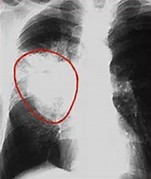

非小细胞肺癌患者在接受第一代或第二代TKI治疗后,约50-60%的患者将发生T790M耐药突变,这种情况下,二线药物、靶向T790M突变的奥希替尼,可进一步延长化疗的使用时间。随着越来越多的有针对性的治疗方法面市,临床医生必须了解如何恰当地进行序列治疗,以确保取得最佳疗效。这项真实世界研究有助于我们对耐药突变和序贯治疗有更进一步的理解,为优化治疗方案提供证据。该研究结果预计将在2018年公布。

阿法替尼(afatinib)是勃林格殷格翰的第一个非小细胞肺癌药物,它是表皮生长因子受体(EGFR)和人表皮生长因子受体2 (HER2)酪氨酸激酶的强效、不可逆的双重抑制剂,是目前一线TKI药物。但如前所述,约半数患者在接受治疗后会发生耐药性突变——T790M突变,使得靶向T790M的药物变得十分重要。在这一领域首先获得FDA批准的是阿斯利康的非小细胞肺癌药物——奥希替尼(osimertinib),目前该药在这一领域占据明显的优势,而其他公司也在加紧研发针对该靶点的药物。值得一提的是勃林格殷格翰的针对T790M突变药物BI1482694 (Olmutinib)在2015年获得了FDA突破性疗法认定,并先于奥希替尼在韩国上市,但在韩国应用中,有3名患者发生严重不良反应,并有2人死亡,因此该药目前已被勃林格殷格翰交换给原研发企业韩美制药有限公司进行全球开发和商业化。除了这两个闪闪发光的EGFR-T790M突变靶向药物之外,Clovis Oncology公司的的EGFR-T790M靶向药rociletinib (CO-1686)由于受试病人出现了恶化反应被FDA延迟批准,目前已放弃研发。